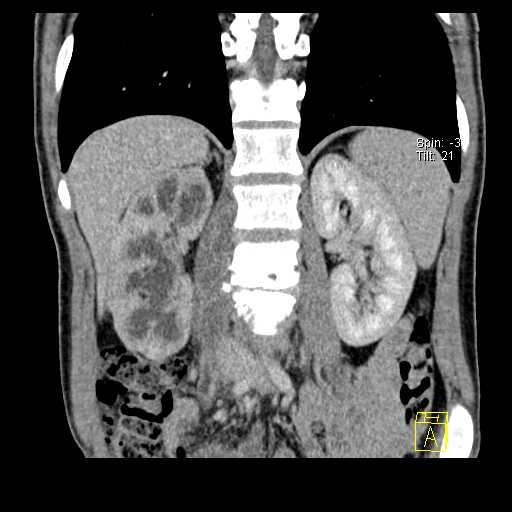

Нефрокальциноз (кальцинаты в почках) - это отложения солей кальция в почечных тканях с образованием конкрементов различного размера . Конкременты представляют собой твердые включения из солей в области инфильтрационного воспаления . Нефрокальциноз может возникать как сопутствующее заболевание при дисфункции почек и мочевыводящей системы .

Кальцинаты в почках - это кристаллы из солей кальция, которые откладываются в почечной ткани и приводят к рубцеванию органов . В 8 из 10 случаев в паренхиме и мозговом веществе почки . . .